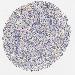

LYMPHOMA - Protein expressioni

A mouse-over function shows sample information and annotation data. Click on an image to view it in a full screen mode. Samples can be filtered based on level of antibody staining by selecting one or several of the following categories: high, medium, low and not detected. The assay and annotation is described here.

Antibody HPA003142

Staining

High

Medium

Low

Not detected

Intensity

Strong

Moderate

Weak

Negative

Quantity

>75%

75%-25%

<25%

None

Location

Nuclear

Cytoplasmic/membranous

Cytoplasmic/membranous,nuclear

Malignant lymphoma, non-Hodgkin's type, High grade

Hodgkin's disease, NOS

Malignant lymphoma, non-Hodgkin's type, Low grade